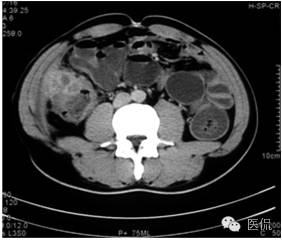

平扫示肝下缘局部隆突,密度减低,内部密度不均,隐约见分隔影,其下缘与升结肠界线消失,肠壁增厚、模糊。